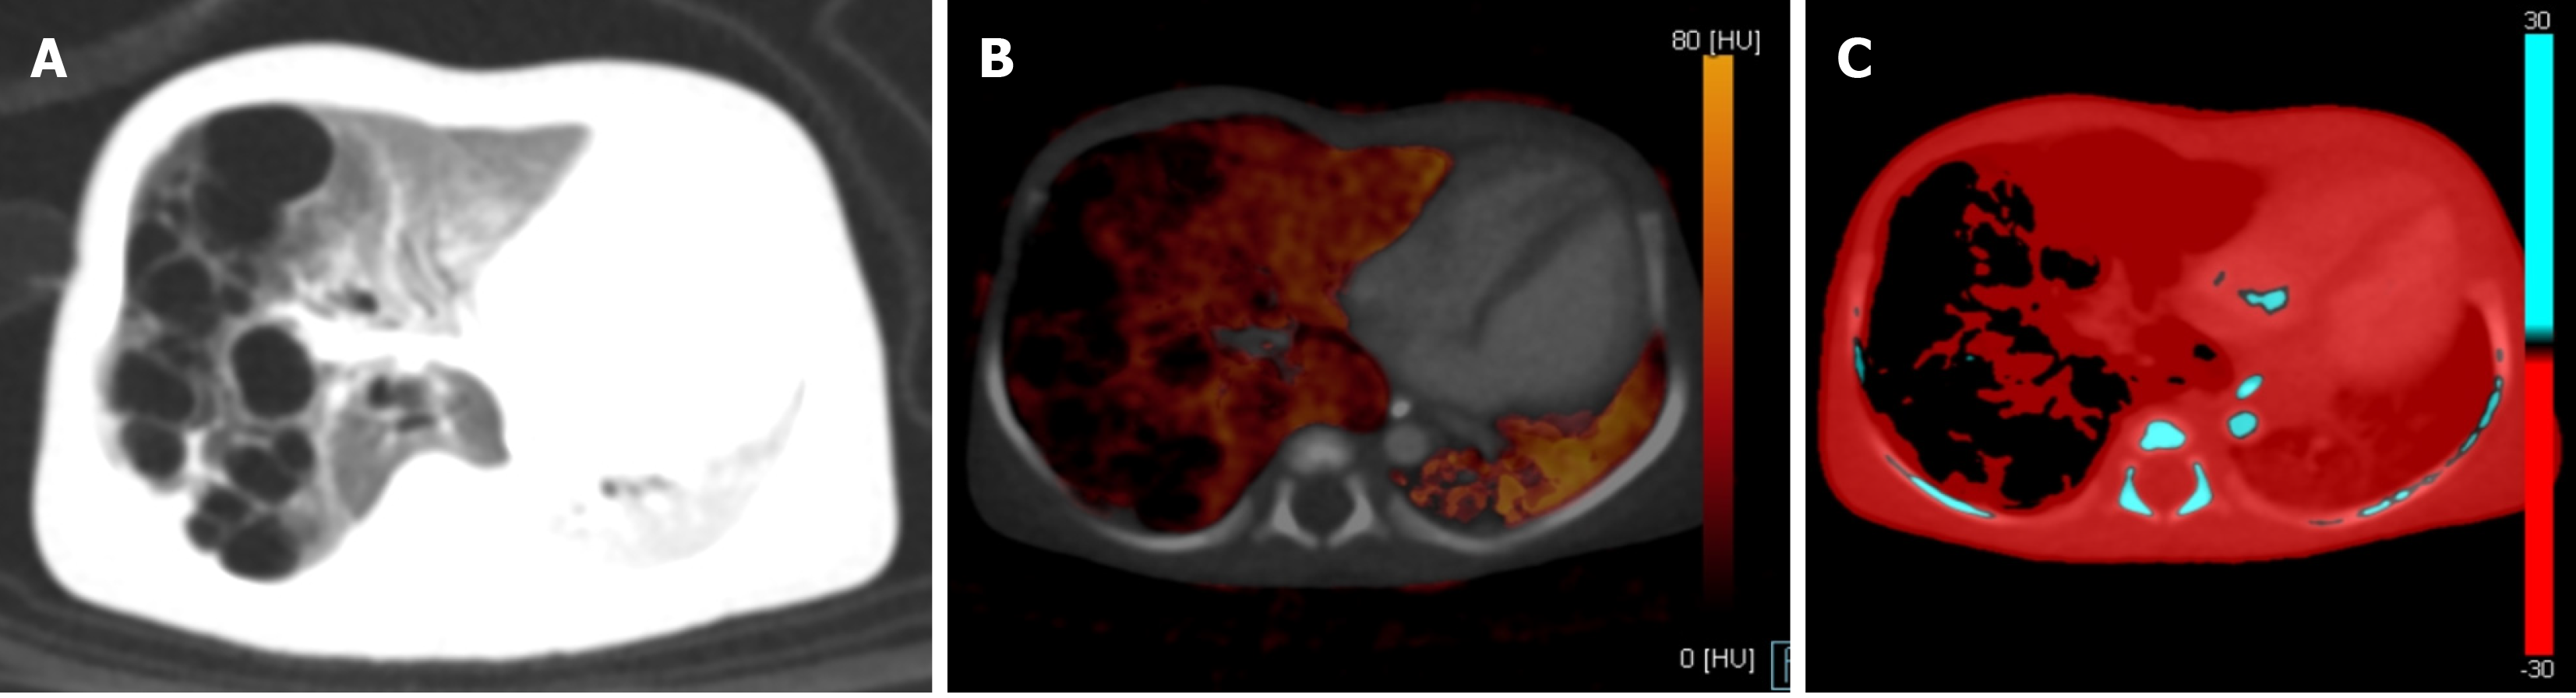

Figure 8 Axial sections of CT pulmonary angiography in a 2-month-old female with infective endocarditis.

A: Complete occlusion of the left pulmonary artery by a thrombus on blended contrast image; B: Complete occlusion of the left pulmonary artery by a thrombus on low kV (80 kV) image, showing increased contrast in the vasculature; C: Lung vessel image showed blue color-coded right pulmonary artery (white arrow) with thrombus being color-coded red in the left pulmonary artery (black arrow), suggesting diminished iodine content; D: Lung blood volume image showed diffusely reduced perfusion in the left lung as compared with the right lung.